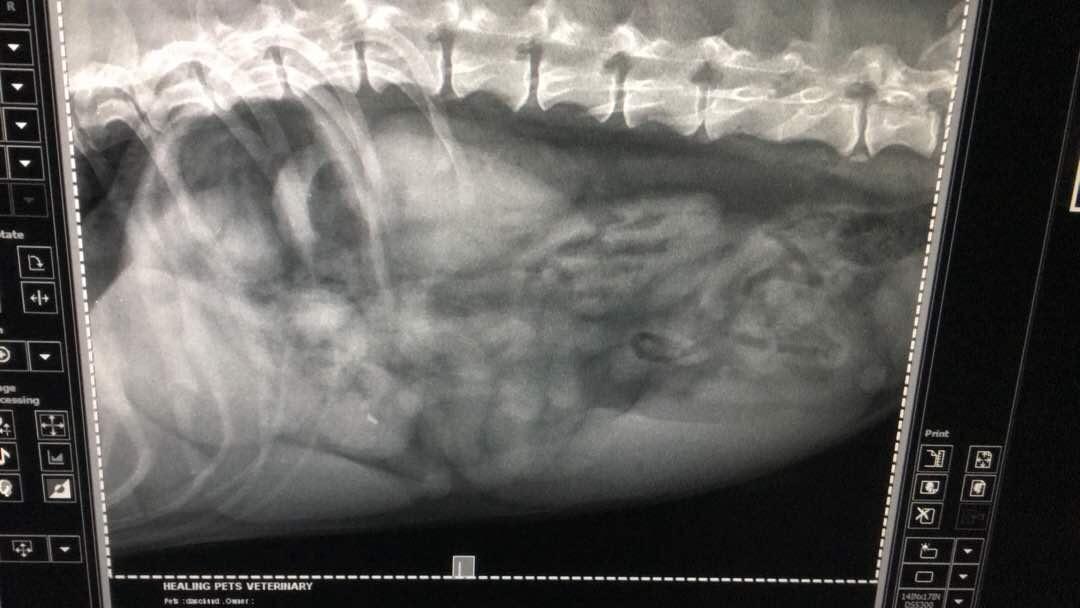

My 7-year old male dachshund is having bloody stool for the last 2 days, today went for X-ray and the vet couldn't indicate what is in his stomach and whether is a serious matter. Sincerely need your precious advice, I'm so worried now.

Hi there and thank you for using pet coach to address your concern. The x-rays that you provided show what looks to be foreign material in the stomach. It looks very similar to pieces of a ball with the rounded edges. This does not appear to be ingested food based on the appearance and shape period while not serious at the moment, one of these could pass from the stomach into the intestines and cause serious problems. I would consider rechecking the X-ray a few hours after the previous x-rays have been taken to see if there has been any change in the pattern. If there is no change in the pattern, I would suggest taking pixie in for surgery to have the abdomen explored. Prior to the surgery, you can also have an abdominal ultrasound performed to help confirm foreign material in the stomach. I hope this helps guide you in the right direction. Please feel free to contact you any other questions or concerns you may have